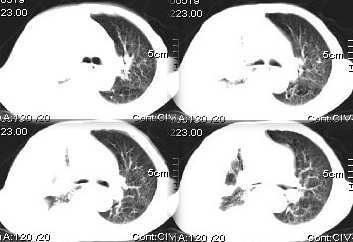

病灶在右上叶支气管的后段旁,成类圆形,约2.3厘米大小,其内见钙化密度区,病灶平扫为77,强化为87.左肺上叶尖后段沿血管支气管分布见小结节.我认为右上叶后段支气管开口有截断.我首先考虑是右中央型肺癌伴右恻大量胸腔积液,但左肺的病变我真的有的不好解释,希望各位战友继续讨论,不对之处望指出!!谢谢!!!

右肺毁损萎陷,其内可见钙化灶、残存空腔及支气管影。左上叶可见多发小结节影。纵隔左移,其内未见肿大淋巴结。右侧胸腔大量积液。考虑:肺结核并右肺毁损;右侧胸腔大量积液。

右侧大量胸腔积液伴右肺压迫性肺不张,左上叶结核.

左上肺炎性或tb可以排外转移。

右上叶后段开口处可见约3cm·3cm大小的肿块,边缘较光滑,无明显分叶且有钙化,右上叶支气管后壁受侵不明显,加上左上叶病灶。我首先考虑肺结核,胸腔积液。右肺不张。还是建议支气管镜检查,或者胸水检查。

右后段处示一肿块但无明显肺癌强化方式,其内尚见钙化,胸膜亦无结节样增厚,再加上左肺结核表现(支血束结节样增粗不确切),则更支持结核伴大量胸液表现。